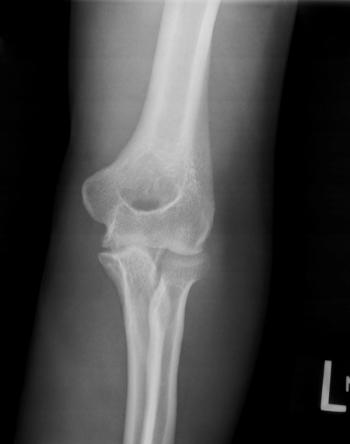

23-year-old male with a known undisclosed disease presents with left elbow pain.